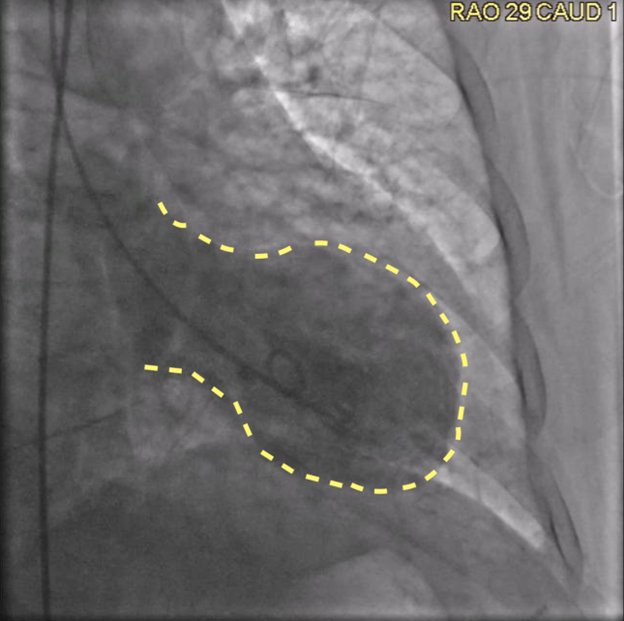

A left heart catheterization revealed a pattern of apical ballooning consistent with stress cardiomyopathy (Figure 2) and a severely depressed left ventricular ejection fraction of 10%. Significant obstructive triple-vessel coronary artery disease was noted with poor collateral circulation (Figures 3-4). No evident left ventricular outflow obstruction. An intra-aortic balloon pump (IABP) was placed, while coronary interventions were held at that time. On the second day of hospitalization, the patient developed intermittent high-grade AV block with hemodynamic instability which progressed to persistent complete heart block (CHB) (Figure 5). Medical management and transcutaneous pacing were initiated until transvenous pacing was achieved. The IABP was later exchanged for an Impella device due to refractory cardiogenic shock and worsening vasopressor requirements.

Figure 2: Coronary angiogram, right anterior oblique, caudal view revealing classical apical ballooning, as outlined with yellow striped line.